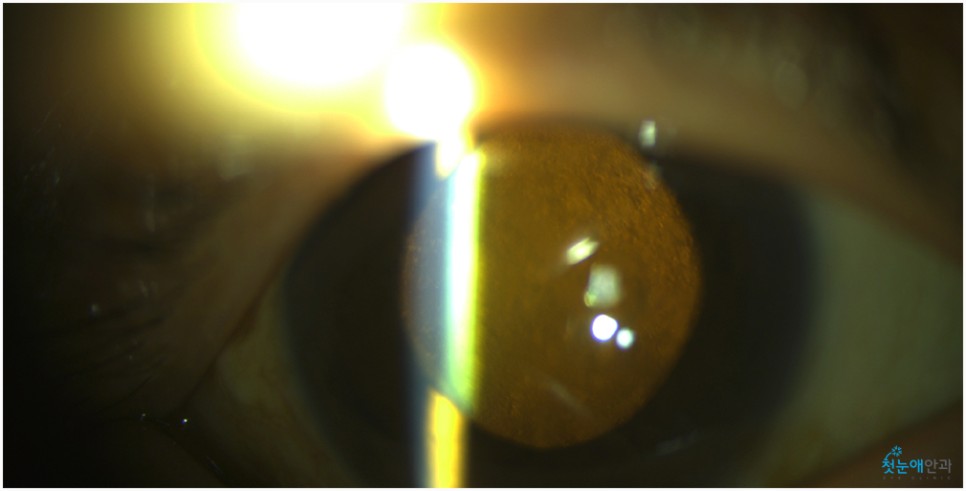

노안 수술 안과에 내원하셨을 때 오른쪽 눈이 잘 보이지 않는다고 말씀하셨습니다.이에 첫눈 애안과 장비를 통해 조사한 결과 이미 백내장 진행이 상당하고 눈 밑 망막 관찰이 어려울 정도로 흐릿한 상태였습니다.

눈이 침침해서 잘 보이지 않았던 것은 올해 초부터라고 말씀하셨습니다.진단 결과 백내장 B) N5CO(+++) PSC(+++) 단계에 해당되며 이는 매우 심한 정도여서 예전에는 맑은 수정체였으나 지금은 혼탁하고 진한 갈색으로 바뀌었습니다.참고로 백내장 초기라면 약물 사용으로 진행을 늦출 수 있었을 것 같은데, 노안수술안과를 방문해주신 환자들은 너무 많은 진행이 있었기 때문에 수술이 필요했습니다.

백내장이 상당히 진행되면 수정체가 흐려져 눈 아래의 망막 관찰이 어렵습니다.때문에 사진을 찍어 검사해봐야 하는데 위와 같이 흐릿한 사진이 찍혀 사실상 망막 관찰이 어렵습니다.뿐만 아니라 심한 백내장은 부분마취 수술 진행이 어려워 안구마취나 전신마취로 수술하거나 종합병원으로 전환해 수술해야 합니다.뿌옇게 변했는데도 그냥 놔두면 위 사진처럼 더 심해져 시력이 저하되는 상황까지 이어지게 됩니다.